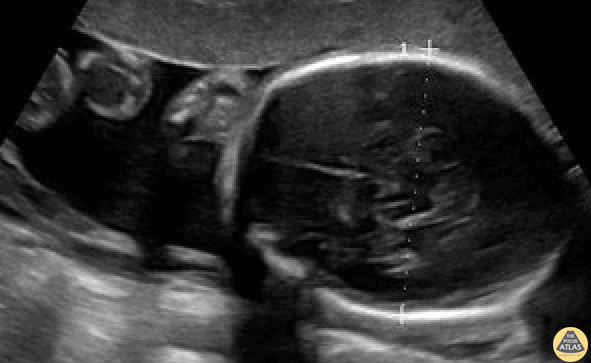

OB/Gyn - Biparietal diameter (BPD) measurement in a 26-week pregnancy.

BPD should be measured in the axial plane, perpendicular to the falx cerebri, and from the outer edge of the near calvarial wall to the inner edge of the far calvarial wall. Contributors: Stephen Holihan (MD); Dillon Nerland (MD); Madison Waddell (MS4)